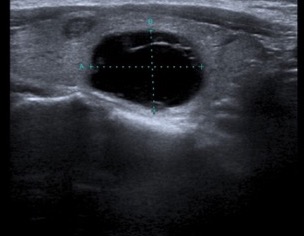

L’ipoecogenicità è dovuta all’aumento della quota cellulare rispetto alla colloide. Una marcata ipoecogenicità (simile a quella dei muscoli pre-tiroidei) è associata ad aumento del rischio di malignità con elevata specificità (fig. 10); talvolta può essere difficile distinguerla dall’ecogenicità di una raccolta liquida densa, ma l'uso del Doppler e i cambiamenti di posizione sono dirimenti nei casi dubbi. È importante differenziarla dalla debole ipoecogenicità (valutata rispetto al parenchima tiroideo circostante), perché questa è comune tanto alla patologia maligna che benigna e ha una minore accuratezza diagnostica (fig. 11).

Figura 10. Nodulo tiroideo marcatamente ipoecogeno a margini regolari in sede para-carotidea. In caso di marcata ipoecogenicità può essere difficile distinguere un nodulo solido da una raccolta liquida densa. L'uso dell'ecodoppler e i cambiamenti di posizione sono dirimenti nei casi dubbi.